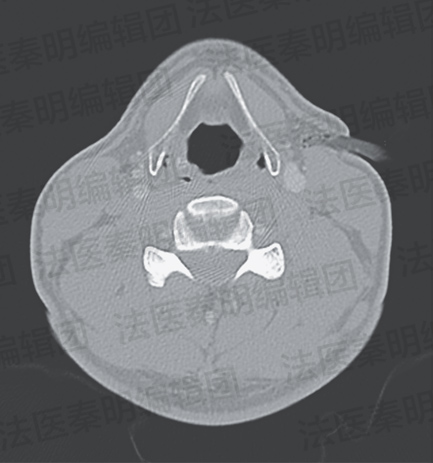

一位40岁骑山地自行车爬山的人,不慎摔倒后,被一根直径2cm的树枝刺入了颈部,当时他没有试图自行将树枝取出,而是独自来到了附近医院的急诊部门。急诊医生对其进行了CT(计算机断层扫描)检查,发现异物位于左侧颈部,刺入颈部软组织中的部分位于甲状软骨水平,穿过颈阔肌至胸锁乳突肌前缘,没有损伤血管与气道。医生决定对该患者施行手术,异物被取出,创道被充分探查和清洗,并被缝合关闭,手术后患者恢复顺利,并痊愈出院。

颈部外伤患者 图源:参考文献[3]

颈部外伤患者CT 图源:参考文献[3]